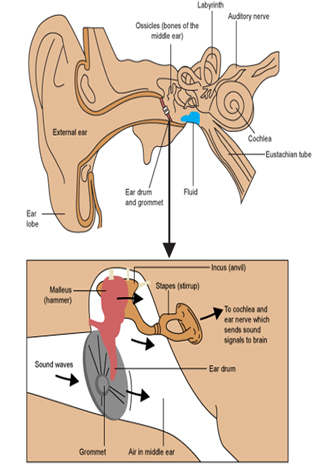

What are grommets cheap

What are grommets cheap, Grommets Mr Daniel Tweedie Consultant Paediatric ENT Surgeon cheap

What is a grommet ent4kids cheap, Grommets ENT Info cheap, Grommets Mr Daniel Tweedie Consultant Paediatric ENT Surgeon cheap, Grommets KidsHealth NZ cheap, Grommets KidsHealth NZ cheap, Description of operation for grommet ventilation tube insertion cheap, Grommets A decision making aid for parents ENT UK cheap, Grommets aarontrinidade cheap, Glue Ear Middle Ear Infections and Grommets Dr Sean Flanagan cheap, Ear Grommets ENT Clinic Sydney cheap, Grommets Adelaide Specialist ENT Surgeon Paul Varley ENT cheap, Ear Grommets ENT Clinic Sydney cheap, Grommets healthdirect cheap, Grommet Insertion Child Parkside Hospital cheap, Treatment of glue ear with grommets Great Ormond Street Hospital cheap, Grommets North View ENT Dr Sebastian Ranguis ENT Surgery cheap, Grommets Children s Health Queensland cheap, Grommets cheap, Grommets Ear Nose Throat Newcastle cheap, What are Grommets and how do they work Dr. Shalina Ray cheap, Grommets And The Benefits of Using Them cheap, Middle ear ventilation tubes grommets Dr Bridget Clancy ENT cheap, Grommets Mr Daniel Tweedie Consultant Paediatric ENT Surgeon cheap, Glue Ear Grommets Western ENT cheap, Grommet Insertion Surgery India Cost Grommet Insertion Surgery Abroad cheap, James Rainsbury Plymouth ENT specialist consultant Private cheap, How much does ear grommet surgery cost in Australia cheap, Grommets for glue ear treatment Essex London ENT cheap, Grommets Ear Nose Throat Newcastle cheap, Water precautions following grommets Dr Jeeve ENT Specialist cheap, All you need to know about grommets You cheap, Sydney Paediatric ENT Surgeon For Ear Grommets MY ENT cheap, Grommets MESHGuides cheap, Grommets aarontrinidade cheap, Grommets ENT Doctor Cape Town Dr Shabeer Ebrahim cheap.

What is a grommet ent4kids cheap, Grommets ENT Info cheap, Grommets Mr Daniel Tweedie Consultant Paediatric ENT Surgeon cheap, Grommets KidsHealth NZ cheap, Grommets KidsHealth NZ cheap, Description of operation for grommet ventilation tube insertion cheap, Grommets A decision making aid for parents ENT UK cheap, Grommets aarontrinidade cheap, Glue Ear Middle Ear Infections and Grommets Dr Sean Flanagan cheap, Ear Grommets ENT Clinic Sydney cheap, Grommets Adelaide Specialist ENT Surgeon Paul Varley ENT cheap, Ear Grommets ENT Clinic Sydney cheap, Grommets healthdirect cheap, Grommet Insertion Child Parkside Hospital cheap, Treatment of glue ear with grommets Great Ormond Street Hospital cheap, Grommets North View ENT Dr Sebastian Ranguis ENT Surgery cheap, Grommets Children s Health Queensland cheap, Grommets cheap, Grommets Ear Nose Throat Newcastle cheap, What are Grommets and how do they work Dr. Shalina Ray cheap, Grommets And The Benefits of Using Them cheap, Middle ear ventilation tubes grommets Dr Bridget Clancy ENT cheap, Grommets Mr Daniel Tweedie Consultant Paediatric ENT Surgeon cheap, Glue Ear Grommets Western ENT cheap, Grommet Insertion Surgery India Cost Grommet Insertion Surgery Abroad cheap, James Rainsbury Plymouth ENT specialist consultant Private cheap, How much does ear grommet surgery cost in Australia cheap, Grommets for glue ear treatment Essex London ENT cheap, Grommets Ear Nose Throat Newcastle cheap, Water precautions following grommets Dr Jeeve ENT Specialist cheap, All you need to know about grommets You cheap, Sydney Paediatric ENT Surgeon For Ear Grommets MY ENT cheap, Grommets MESHGuides cheap, Grommets aarontrinidade cheap, Grommets ENT Doctor Cape Town Dr Shabeer Ebrahim cheap.